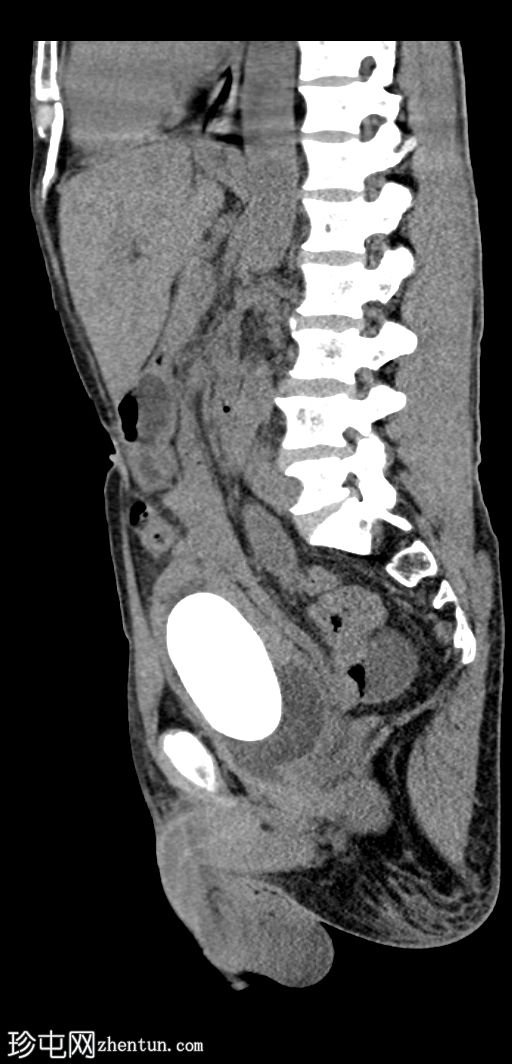

矢状位

平扫

膀胱内可见一枚较大的高密度结石(轴位、冠状位、矢状位),大小约8 × 5.6 × 5.1 cm,伴膀胱壁弥漫性增厚和小憩室。

双侧中重度输尿管肾积水,肾实质厚度减薄,左侧更为明显。双侧输尿管迂曲(右侧、左侧),前列腺尿道轻度扩张。双侧未见肾内或输尿管结石。

本病例展示了一例巨大的膀胱结石导致慢性膀胱出口梗阻,并继发双侧输尿管肾积水。